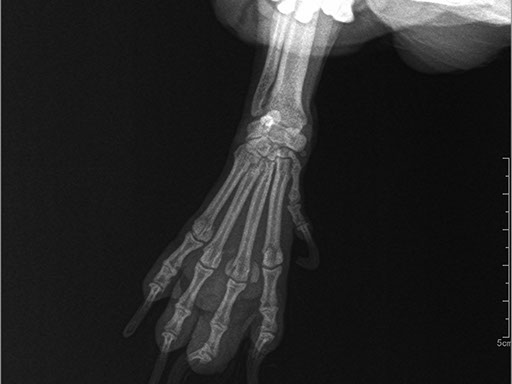

ЦИФРОВОЙ РЕНТГЕН В ВЕТЕРИНАРИИ

Рентген в ветеринарии давно не новинка. Первое руководство по ветеринарной рентгенологии было написано немецким ученым М.Вейзером еще в 1923 году.